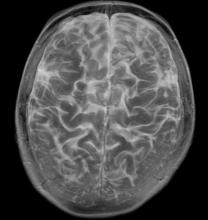

Limiting the amount of radiation absorbed in the hippocampal portion of the brain during whole-brain radiotherapy (WBRT) for brain metastases preserves memory function in patients for up to six months after treatment according to research presented at the American Society for Radiation Oncology’s (ASTRO’s) 55th Annual Meeting.